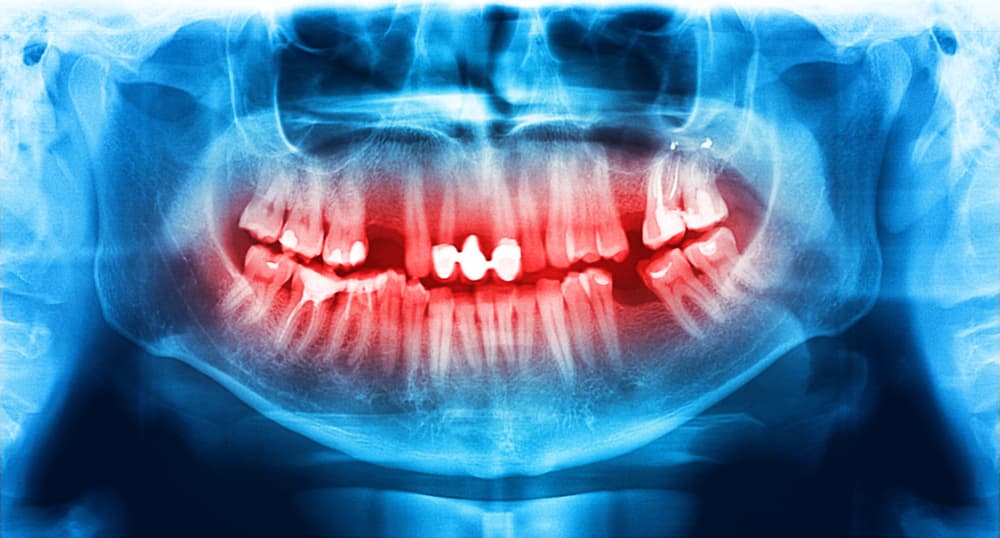

Científicos del Laboratorio de Medicina de la Universidad de Columbia, en Estados Unidos, crearon unos implantes dentales hechos de células madres, que regeneran los dientes en tan sólo dos meses.

Es un método donde se guía a las células madres del cuerpo a un molde tridimensional hecho de materiales naturales, que está integrado en el tejido a tratar. El diente comenzará a crecer en la cavidad, creando una nueva pieza.

Después de ocho semanas, encontraron que el tejido fibroso y el hueso del diente se regeneraron justo donde se pusieron los moldes. Mostraron una integración y crecimiento de dentina, la parte interna del diente, en zonas de la mandíbula.

Para este avance usaron moldes con biomateriales, que son sustancias diseñadas para ser implantadas y reemplazar o restaurar tejidos vivos, de acuerdo al Instituto Nacional de Imagen Biomédica y Bioingeniería, de Estados Unidos.